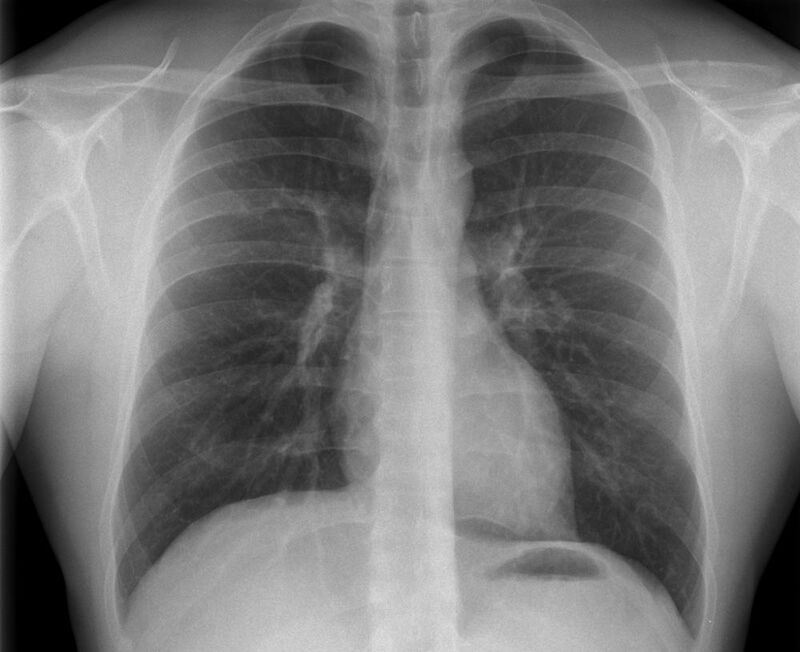

Konventionelles Röntgen

Der Begriff Röntgen, oder auch Röntgendiagnostik bezeichnet ein Verfahren in der Radiologie, bei dem von einer Röntgenröhre elektromagnetische Wellen (Röntgenstrahlen) durch die zu untersuchende Körperregion des Patienten gesendet werden. Je nach Dichte der Gewebeart des Körpers (z.B. Knochen oder Lunge) werden die Röntgenstrahlen im Körper unterschiedlich stark abgeschwächt. Ein digitaler Detektor empfängt dann die Röntgenstrahlen, die in abgeschwächter Form den Körper wieder verlassen haben. Daraus wird das Röntgenbild erzeugt.

Die Röntgenuntersuchung ist weiterhin eine unverzichtbare Basisdiagnostik. Viele Fragen können in der medizinischen Diagnostik mit einer konventionellen Röntgenaufnahme geklärt werden.